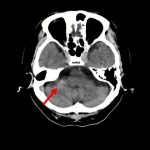

断層撮影

手術前1